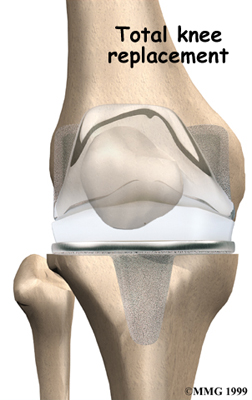

Artificial Knee Replacement

An artificial knee replacement is the ultimate solution for advanced knee OA.

Surgeons prefer not to put a new knee joint in patients younger than 60. This is because younger patients are generally more active and might put too much stress on the joint, causing it to loosen or even crack. A revision surgery to replace a damaged prosthesis is harder to do, has more possible complications, and is usually less successful than a first-time joint replacement surgery.

Related Document: FYZICAL Marietta's Guide to Artificial Joint Replacement of the Knee